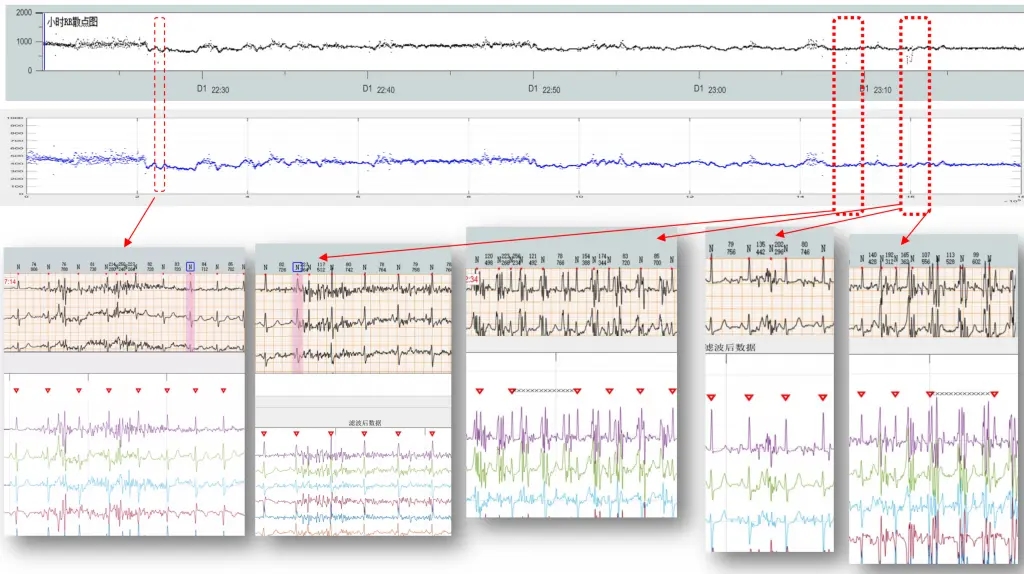

医疗滤波器性能展示

R峰识别准确率展示